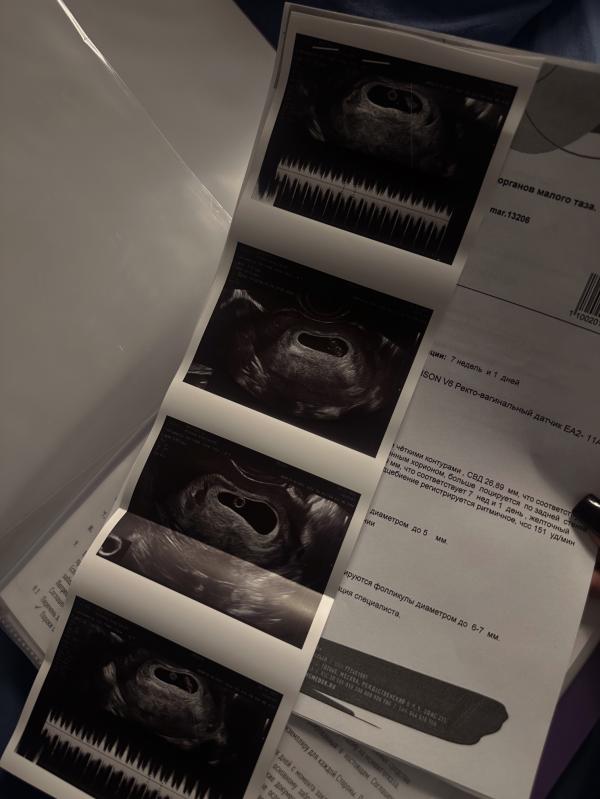

Третье УЗИ🩵

Бусинка растет, сердечко 151 ЧСС, все отлично☺️

А еще намерили шейку сегодня аж 33мм!!! Я в шоке ибо в прошлые два раза она была 26-27, и сказали что возможно и не прийдется зашивать🎊